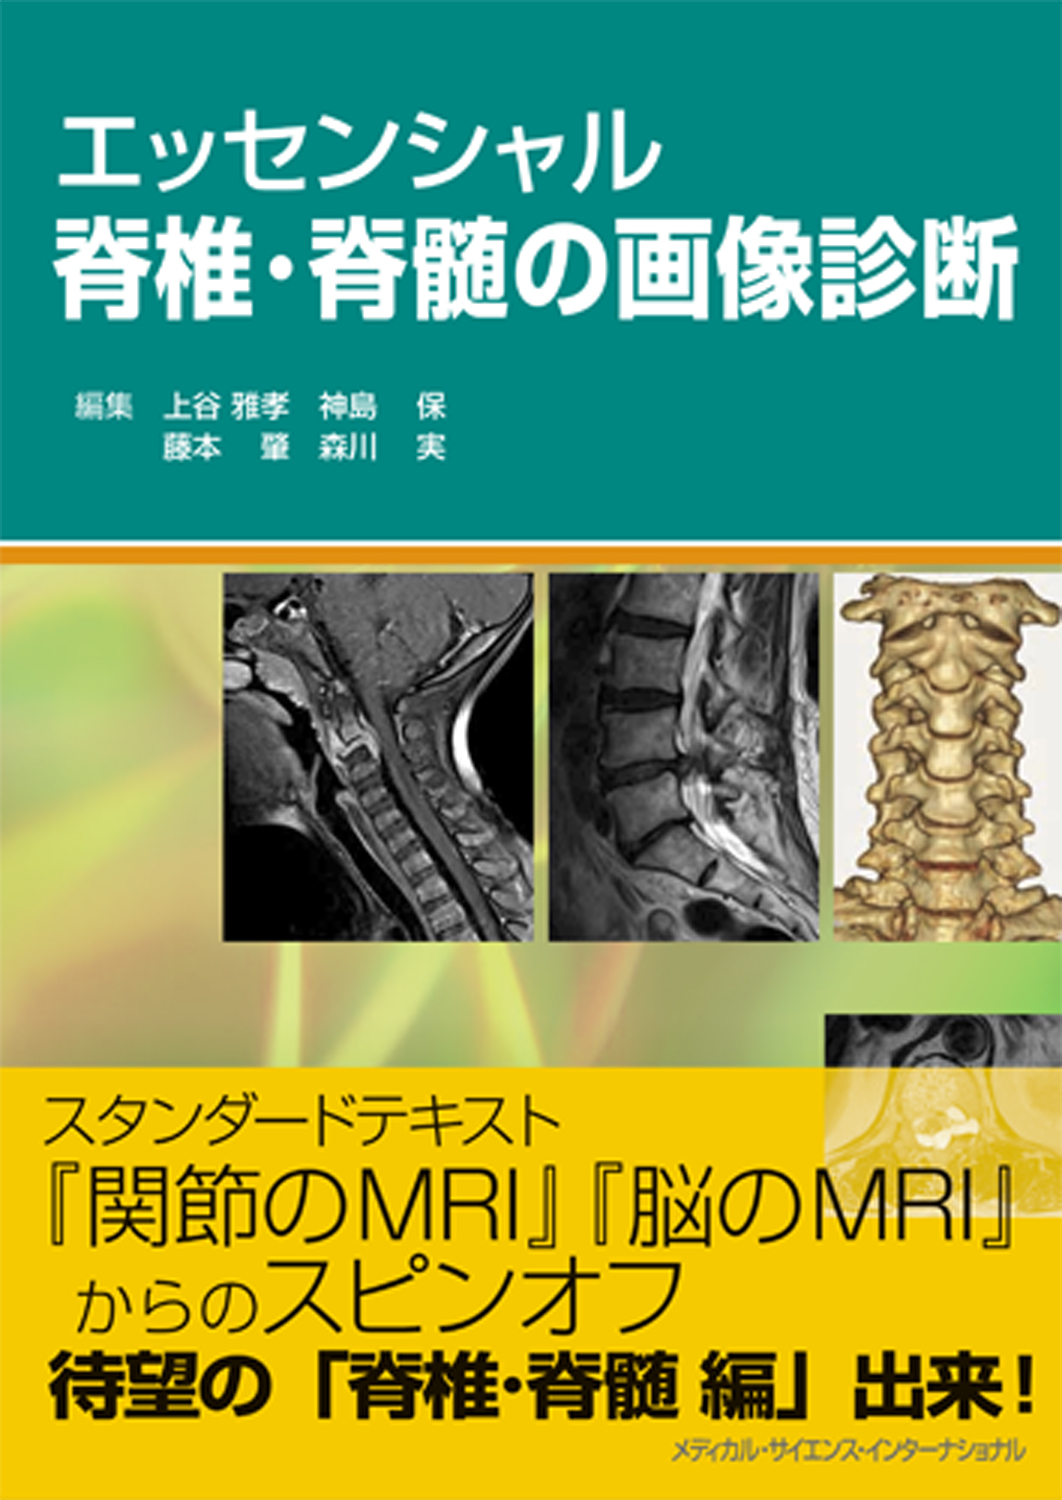

大特価 チラシ 腹部のMRI Amazon | 通販 | |本 力 荒木 | 第3版 医学一般